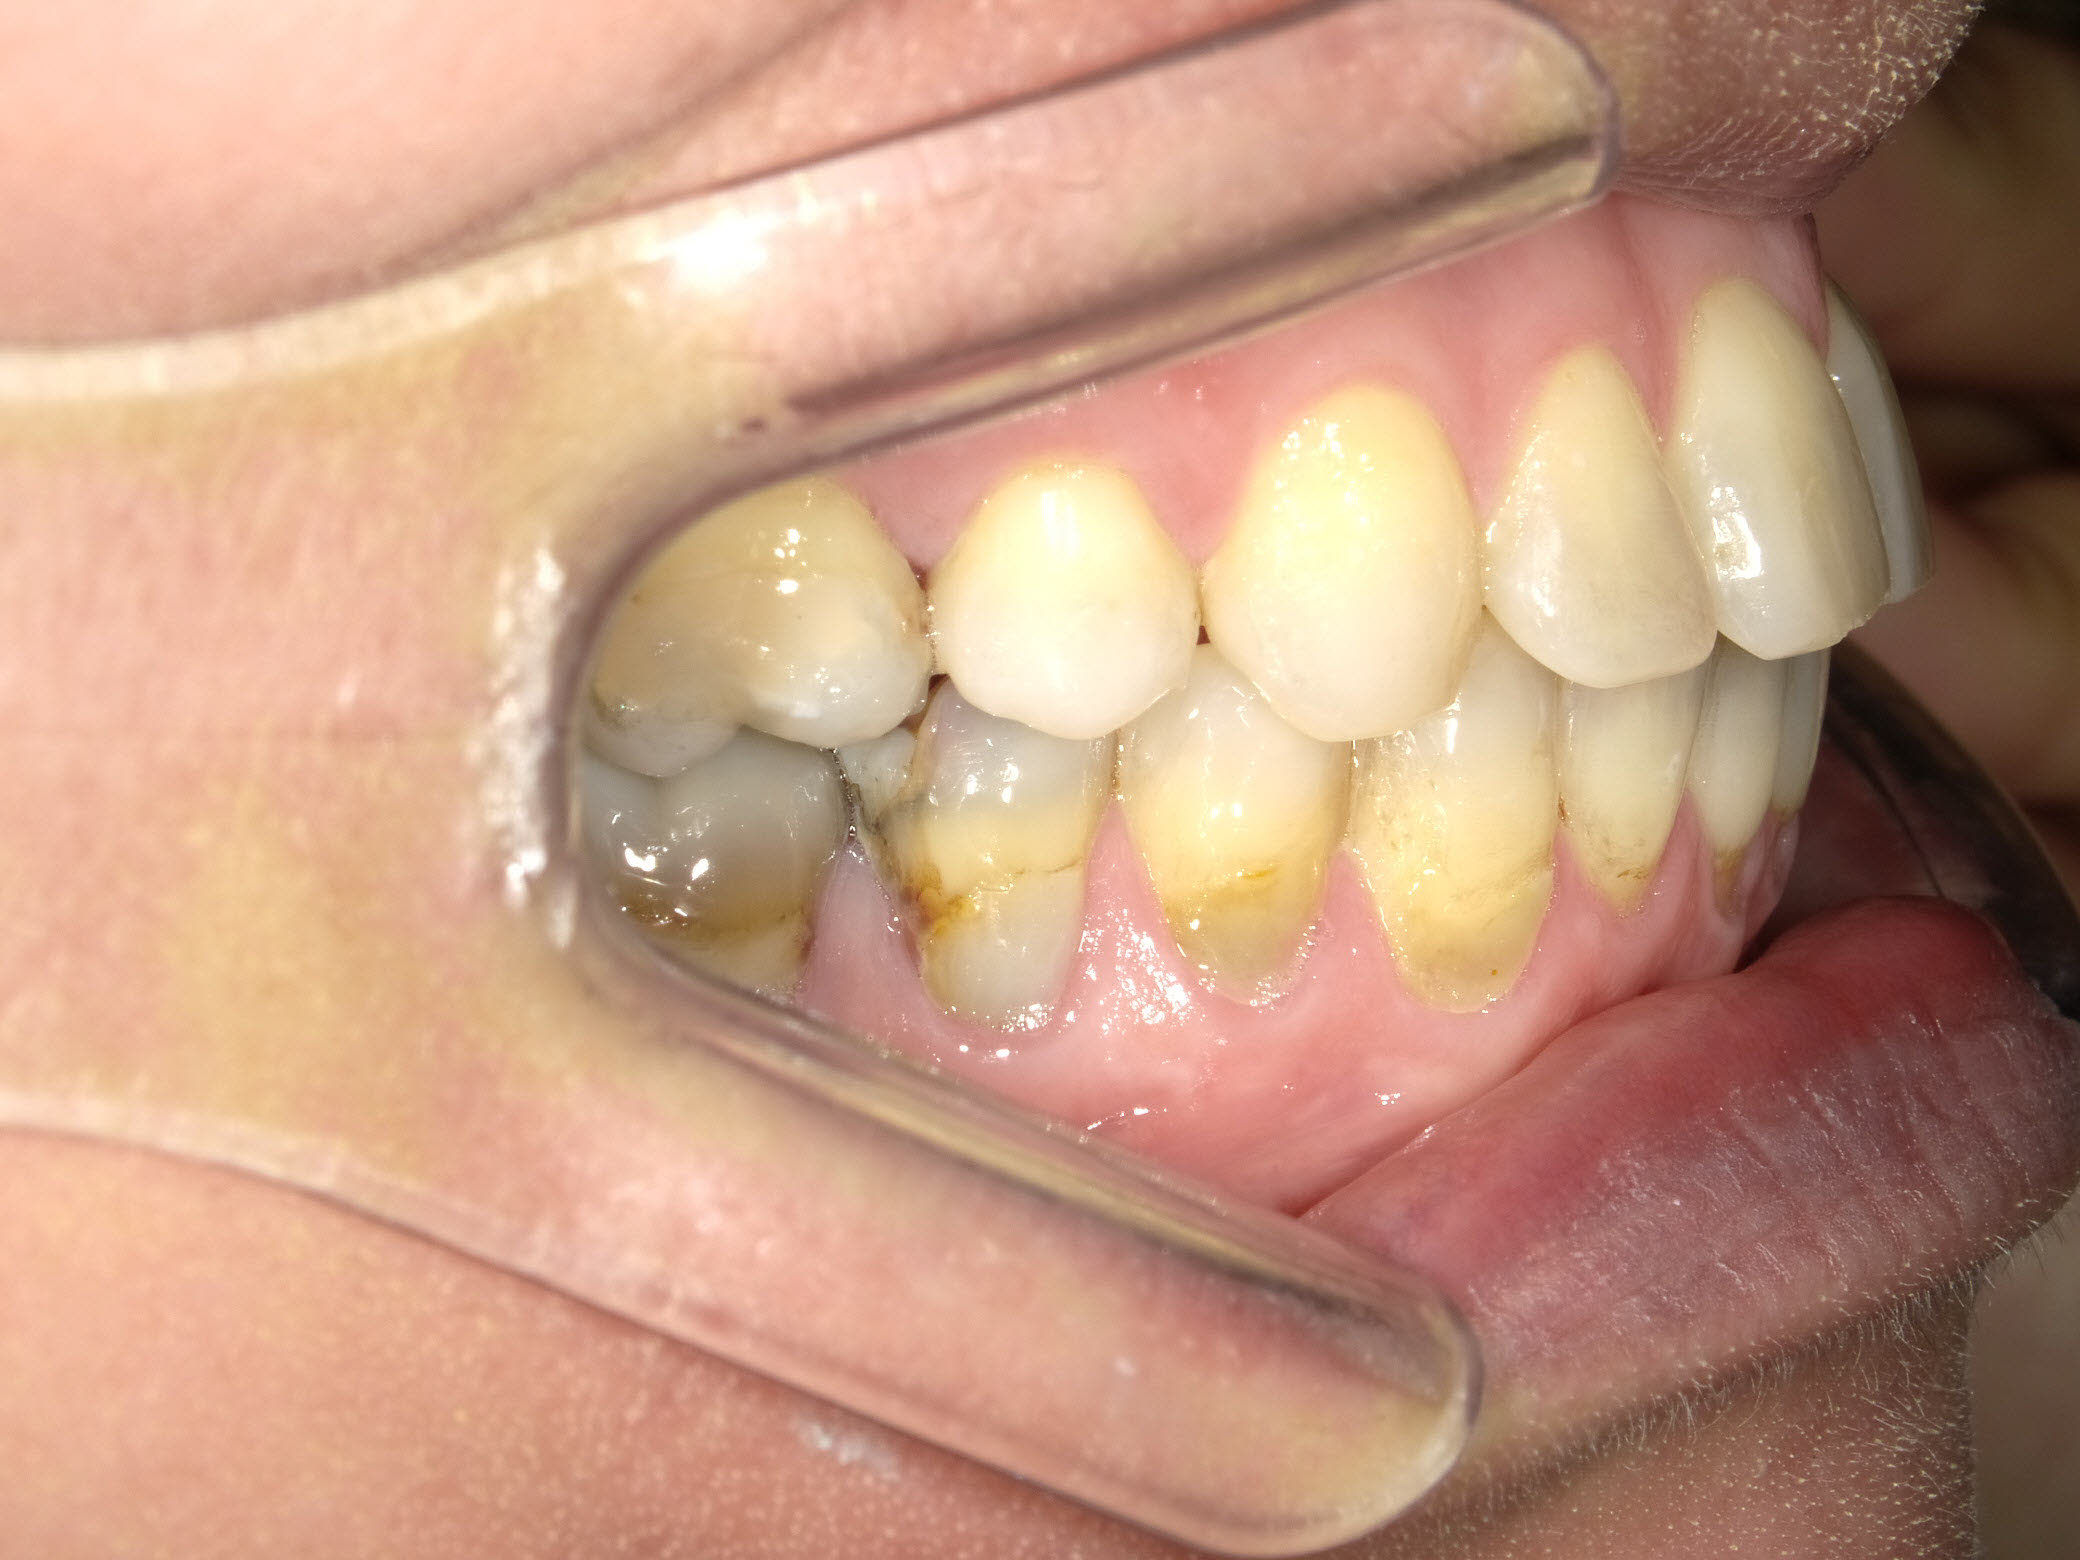

Links Zustand beim Einsetzen der festen Zahnspange, rechts Situation unmittelbar nach der Operation (nach 2 Jahren, 4 Monaten). Der Unterkiefer wurde chirurgisch vorgesetzt und dadurch die Zahnreihen besser in Kontakt gebracht. Die Operation wurde an der Uniklinik Homburg durchgeführt. Eine Feineinstellung der Verzahnung ist aber im Laufe der kieferorthopädischen Nachbehandlung noch erforderlich.